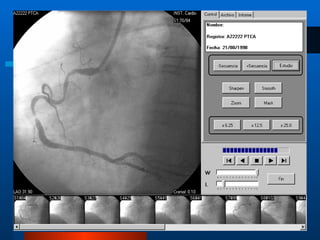

CardioVista Se desarrollo un software específico que decodifica las imágenes cardíacas almacenadas en DICOM,  Permite ver la secuencia de cine en cualquier computadora estándar. El médico puede realizar una serie de procesamientos sobre las imágenes para optimizar el diagnóstico.

Procesos que se realizan mediante CardioVista Avanzar o retroceder en la secuencia, cuadro a cuadro o a la velocidad elegida. Modificar el brillo y el contraste de las imágenes. Aplicar filtros de imagen para resaltar detalles o reducir ruido. Realizar Zoom y paneo de las imágenes. Agregar flechas y anotaciones de texto.

Facilidades de CardioVista Impresión de una o más imágenes en papel. Almacenar todos los estudios en un servidor central para que de esta manera se pueda acceder a ellos desde terminales remotas. Convertir las imágenes DICOM a formatos estándar como BMP o JPEG a efectos de poder incluirlas en informes o presentaciones tipo Powerpoint. Convertir las secuencias DICOM a formato AVI para visualizarlas con programas estándar.

CardioVista Se desarrolloun software específico que decodifica las imágenes cardíacas almacenadas en DICOM, Permite ver la secuencia de cine en cualquier computadora estándar. El médico puede realizar una serie de procesamientos sobre las imágenes para optimizar el diagnóstico.

Procesos que serealizan mediante CardioVista Avanzar o retroceder en la secuencia, cuadro a cuadro o a la velocidad elegida. Modificar el brillo y el contraste de las imágenes. Aplicar filtros de imagen para resaltar detalles o reducir ruido. Realizar Zoom y paneo de las imágenes. Agregar flechas y anotaciones de texto.

Facilidades de CardioVistaImpresión de una o más imágenes en papel. Almacenar todos los estudios en un servidor central para que de esta manera se pueda acceder a ellos desde terminales remotas. Convertir las imágenes DICOM a formatos estándar como BMP o JPEG a efectos de poder incluirlas en informes o presentaciones tipo Powerpoint. Convertir las secuencias DICOM a formato AVI para visualizarlas con programas estándar.